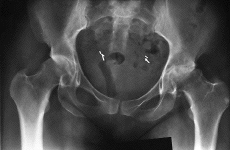

Los trabajos publicados posteriormente, con un seguimiento superior a 5 años, confirmaron el buen comportamiento de este componente. Schmalzried y Harris93 publicaron los resultados obtenidos con 83 cotilos Harris-Galante fresados línea a línea y suplementados con tornillos tras un seguimiento mínimo de 5 años. En esta serie ninguno de los componentes se consideró aflojado, si bien en 22 casos (26,5%) se identificaron líneas radiotransparentes incompletas progresivas. El principal factor relacionado con la aparición de líneas radiotransparentes en esta serie fue la existencia en la radiografía postoperatoria de un espacio radiotransparente entre el lecho óseo acetabular y el respaldo metálico: se detectaron líneas radiotransparentes progresivas en sólo seis (14%) de los 42 componentes sin dicho espacio y en 16 (39%) de los 41 componentes con dicho espacio. Las dos únicas revisiones del componente acetabular fueron motivadas por disociación del polietileno (Fig. 3). Este mismo grupo publicó con posterioridad los resultados obtenidos con 122 cotilos Harris-Galante a presión sin tornillos, con un seguimiento medio de 4 años y 8 meses (mínimo, 4 y máximo, 5,5 años).92 En la mayor parte de los casos la diferencia entre los diámetros de fresa y componente fue de 2 mm (1 mm en casos con hueso poco distensible y 3 ó 4 mm en casos con hueso de escasa consistencia). De nuevo ninguno de los componentes se aflojó, pero se detectaron líneas radiotransparentes progresivas en 31 casos (25%), existiendo la misma correlación que en el trabajo previo con la presencia de espacios radiotransparentes postoperatorios. No se detectaron fracturas acetabulares en ningún caso.

Figura 3. A: Varón de 52 años con coxartrosis secundaria avanzada. B: El mismo paciente 11,5 años después de realizarse una artroplastia total de cadera con un componente acetabular Harris-Galante I; el resultado clínico es excelente.